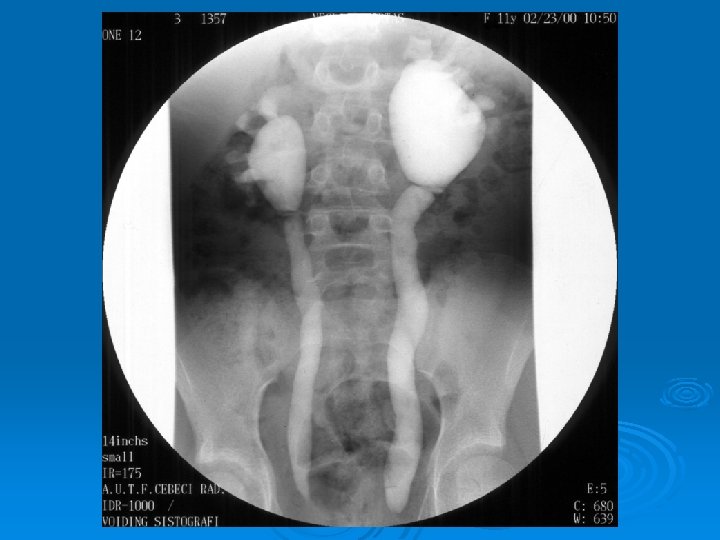

Çocukluk Çağında İdrar Yolu Enfeksiyonları Vezikoüreteral geri kaçış: %30 - 40 %30 -50’sinde üst idrar yollarında genişleme %10 -30’unda böbrekte skar Tıkayıcı anormallik: Kızlarda %2; erkeklerde %10 Tekrarlama: İlk 1 yılda kızlarda %30; erkelerde %15 -20 İlk 5 yılda kızlarda %50; erkeklerde

Çocukluk Çağında İdrar Yolu Enfeksiyonları İZLEMDE TANISAL GÖRÜNTÜLEME YÖNTEMLERİ Ø Miksiyon sistoüretrografisi: Vezikoüreteral geri kaçış (VÜR) görüntülenir. Ø DMSA sintigrafisi: Skar görüntülenir. Ø IVP: Tıkanıklık görüntülenir. Ø DTPA sintigrafisi: Tıkanıklık, böbrek fonksiyonları bozuk hastalarda atılım fonksiyonlarını değerlendirilebilir.